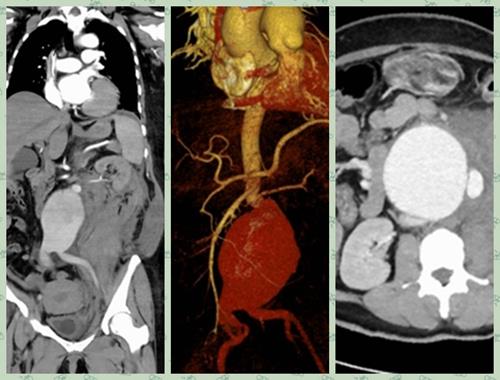

成功救治一例巨大破裂性腹主动脉瘤

普外一科医生雷跃华等人早在一旁严阵以待,立即联系CT室急诊CTA检查,结果提示患者动脉瘤随时有破裂的可能,时间就是生命,情况十分危急。从CT上来看,患者动脉瘤瘤体紧贴双肾动脉,瘤颈短且扭曲,丧失腔内介入治疗机会,雷跃华立即将情况报告给了主任杨玉辉、副主任魏健。得知情况,杨玉辉立即做出指示,患者病情危急,必须立即手术,抢救患者生命。

手术中,发现患者腹膜后出现巨大血肿,约30x15cm大小,瘤体及腹腔内大量积血。时间紧急,立即用血管阻断钳紧贴肾动脉阻断血流,切开瘤体见瘤体后壁一长约6cm破口,成功切除动脉瘤体,并用人工血管进行腹主动脉及双侧髂动脉吻合,吻合口无出血。

腹主动脉瘤是指腹主动脉呈瘤样扩张,通常直径增大50%以上定义动脉瘤。大部分腹主动脉瘤患者都存在控制不良的高血压现象,多数患者无典型的临床症状,常因其他原因查体偶然发现。腹主动脉由于承受的压力及血流量极大,一旦破裂后果不堪设想,被称之为“人体内不定时炸弹”。患者来诊前常因大出血休克而死亡。

腹主动脉瘤破裂前常有突发的腹部剧痛,可伴有腰背部疼痛。患者因大出血可使循环状态迅速恶化而呈休克状态,出现头晕、意识丧失、口渴、手足湿冷、尿量减少等。腹主动脉瘤破裂手术风险极大,死亡率约30-70%,因此及时对本病进行诊治尤为重要。